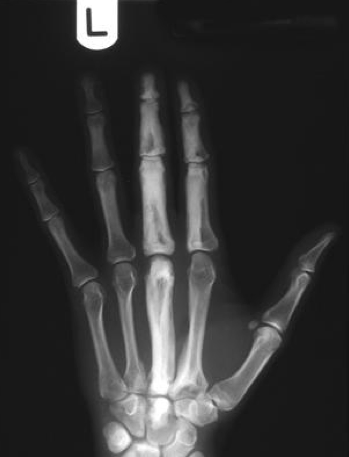

Diagnosis?

Melorheostosis

Benign condition of abnormal periosteal bone formation

“dripping candle wax” appearance with dense hyperostosis that flows along the cortex of the bone